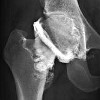

Артрография тазобедренного сустава ребенку

Артография тазобедренного сустава у ребенка - это рентгенологический метод, выполняемый после введения контрастного вещества или воздуха в полость сустава. Артография тазобедренного сустава у ребенка показана при различных формах дисплазии тазобедренного сустава, болезни Пертеса, для определения показаний к хирургическому лечению и его объема. Ценность артрографии заключается в возможности получения достаточно полной информации о состоянии тазобедренного сустава и его элементов, которые не видны на обычных изображениях (внутренние контуры капсулы, состояние суставного пространства, хрящевые компоненты сустава ).